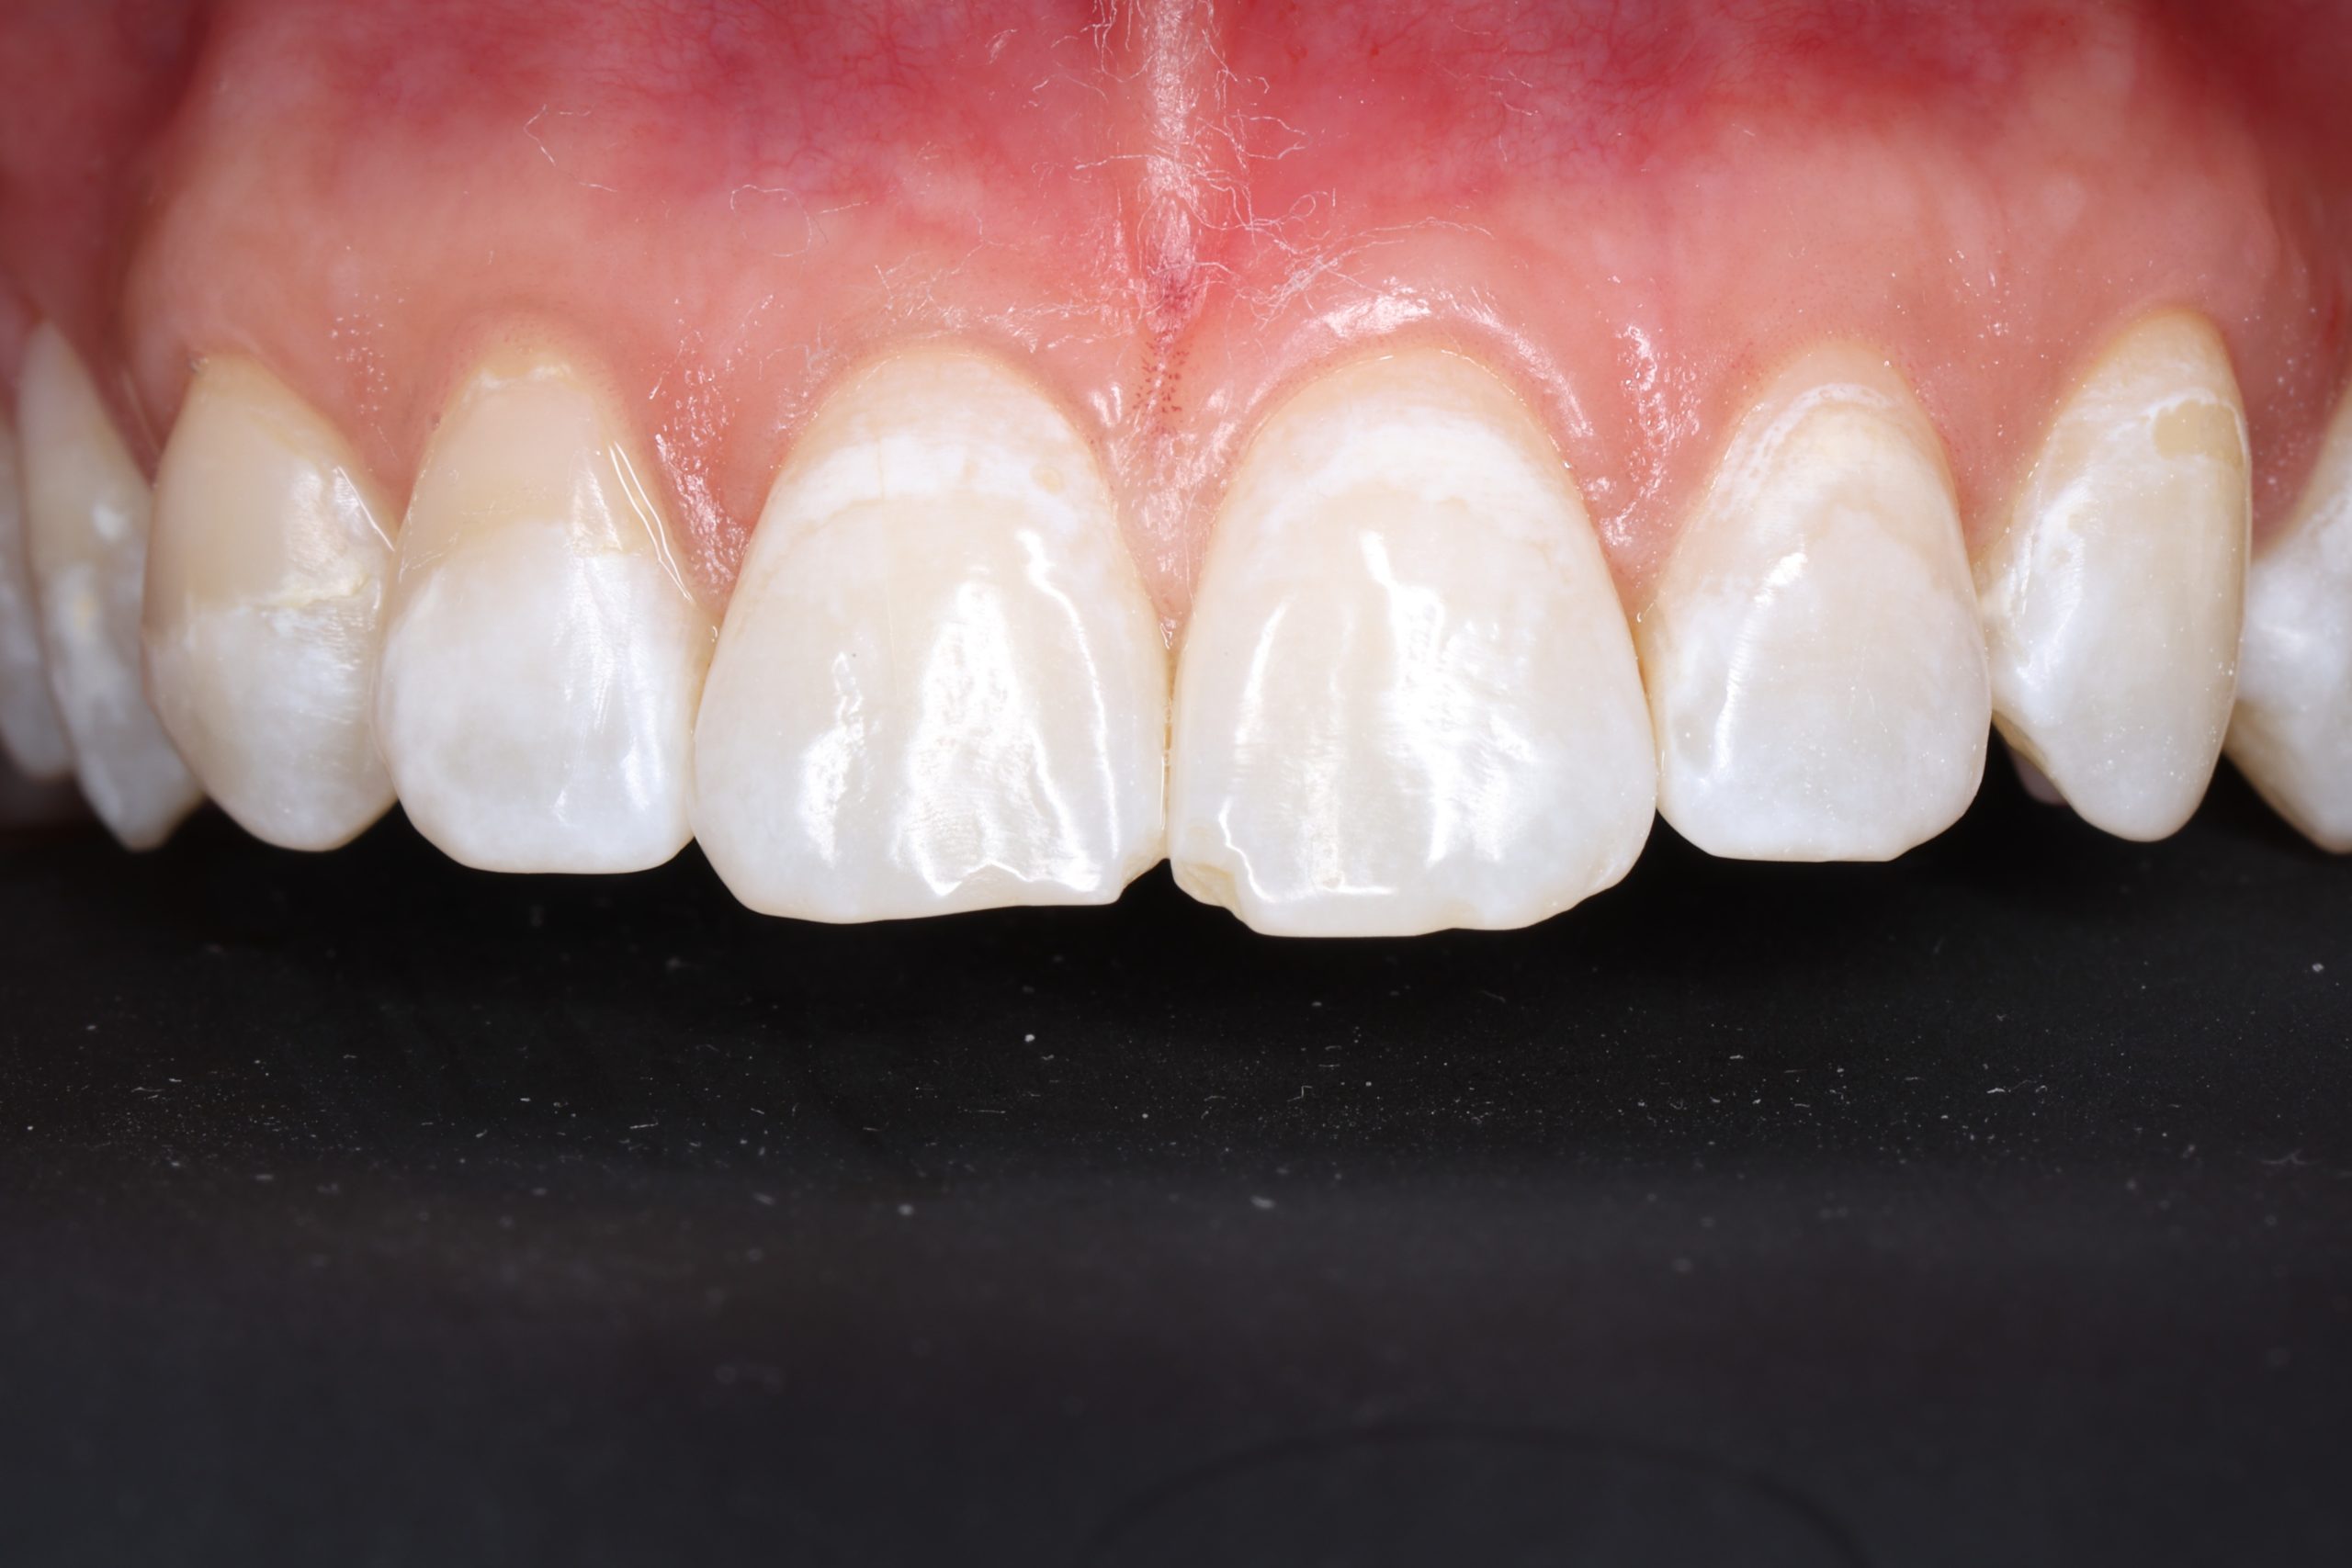

Aesthetic and Natural-Looking

The material matches your enamel, blending into the smile with virtually invisible transitions.

• fixing chipped or worn edges

• closing minor gaps

• correcting tooth shape asymmetry